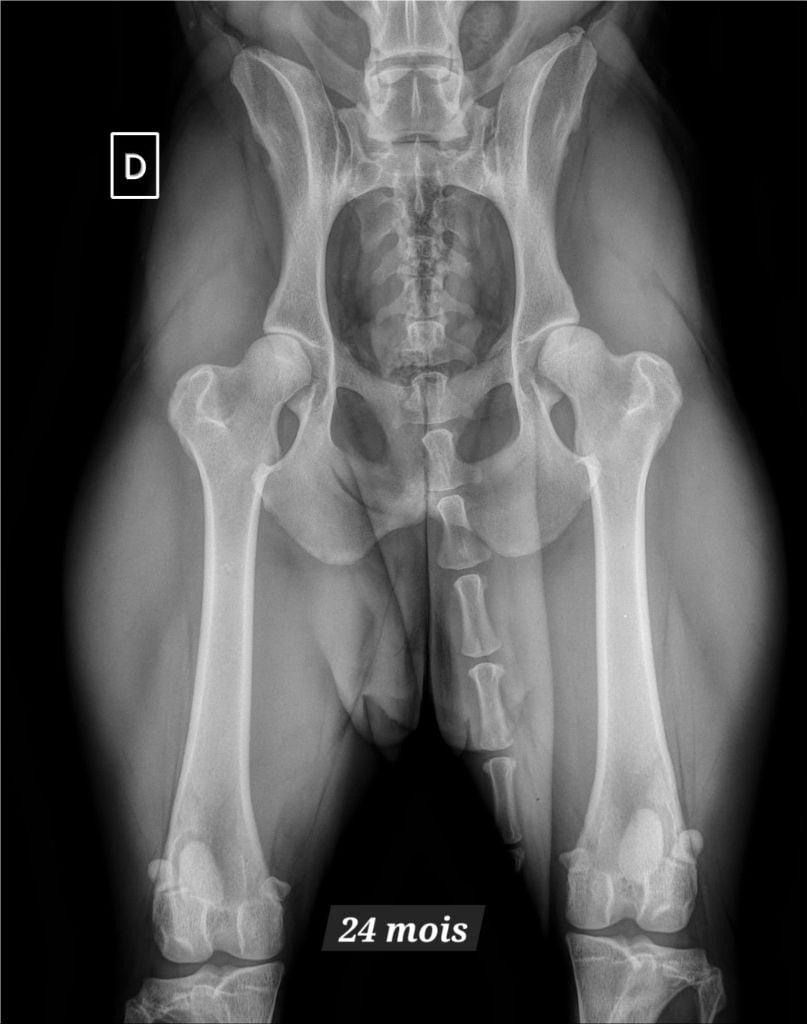

Adn : ADNC Dysplasie des hanches, lecteur français : BC Dysplasie lecteur espagnol : A Indemne de dysplasie renale par échographie : Rdo Indemne de sténoses : Aso pso Spondylose : 0 |